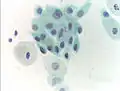

The sample is stained using the Papanicolaou technique, in which tinctorial dyes and acids are selectively retained by cells. Unstained cells cannot be seen adequately with a light microscope. Papanicolaou chose stains that highlighted cytoplasmic keratinization, which actually has almost nothing to do with the nuclear features used to make diagnoses now.

A single smear has an area of 25 x 50 mm and contains a few hundred thousand cells on average. Screening with light microscopy is first done on low (10x) power and then switched to higher (40x) power upon viewing suspicious findings. Cells are analyzed under high power for morphologic changes indicative of malignancy (including enlarged and irregularly shaped nucleus, an increase in nucleus to cytoplasm ratio, and more coarse and irregular chromatin). Approximately 1,000 fields of view are required on 10x power for screening of a single sample, which takes on average 5 to 10 minutes.[63]

Pap tests commonly examine epithelial abnormalities, such as metaplasia, dysplasia, or borderline changes, all of which may be indicative of CIN. Nuclei will stain dark blue, squamous cells will stain green and keratinised cells will stain pink/ orange. Koilocytes may be observed where there is some dyskaryosis (of epithelium). The nucleus in koilocytes is typically irregular, indicating possible cause for concern; requiring further confirmatory screens and tests.